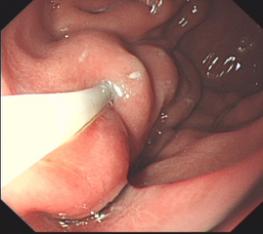

胃底溃疡并出血止血术